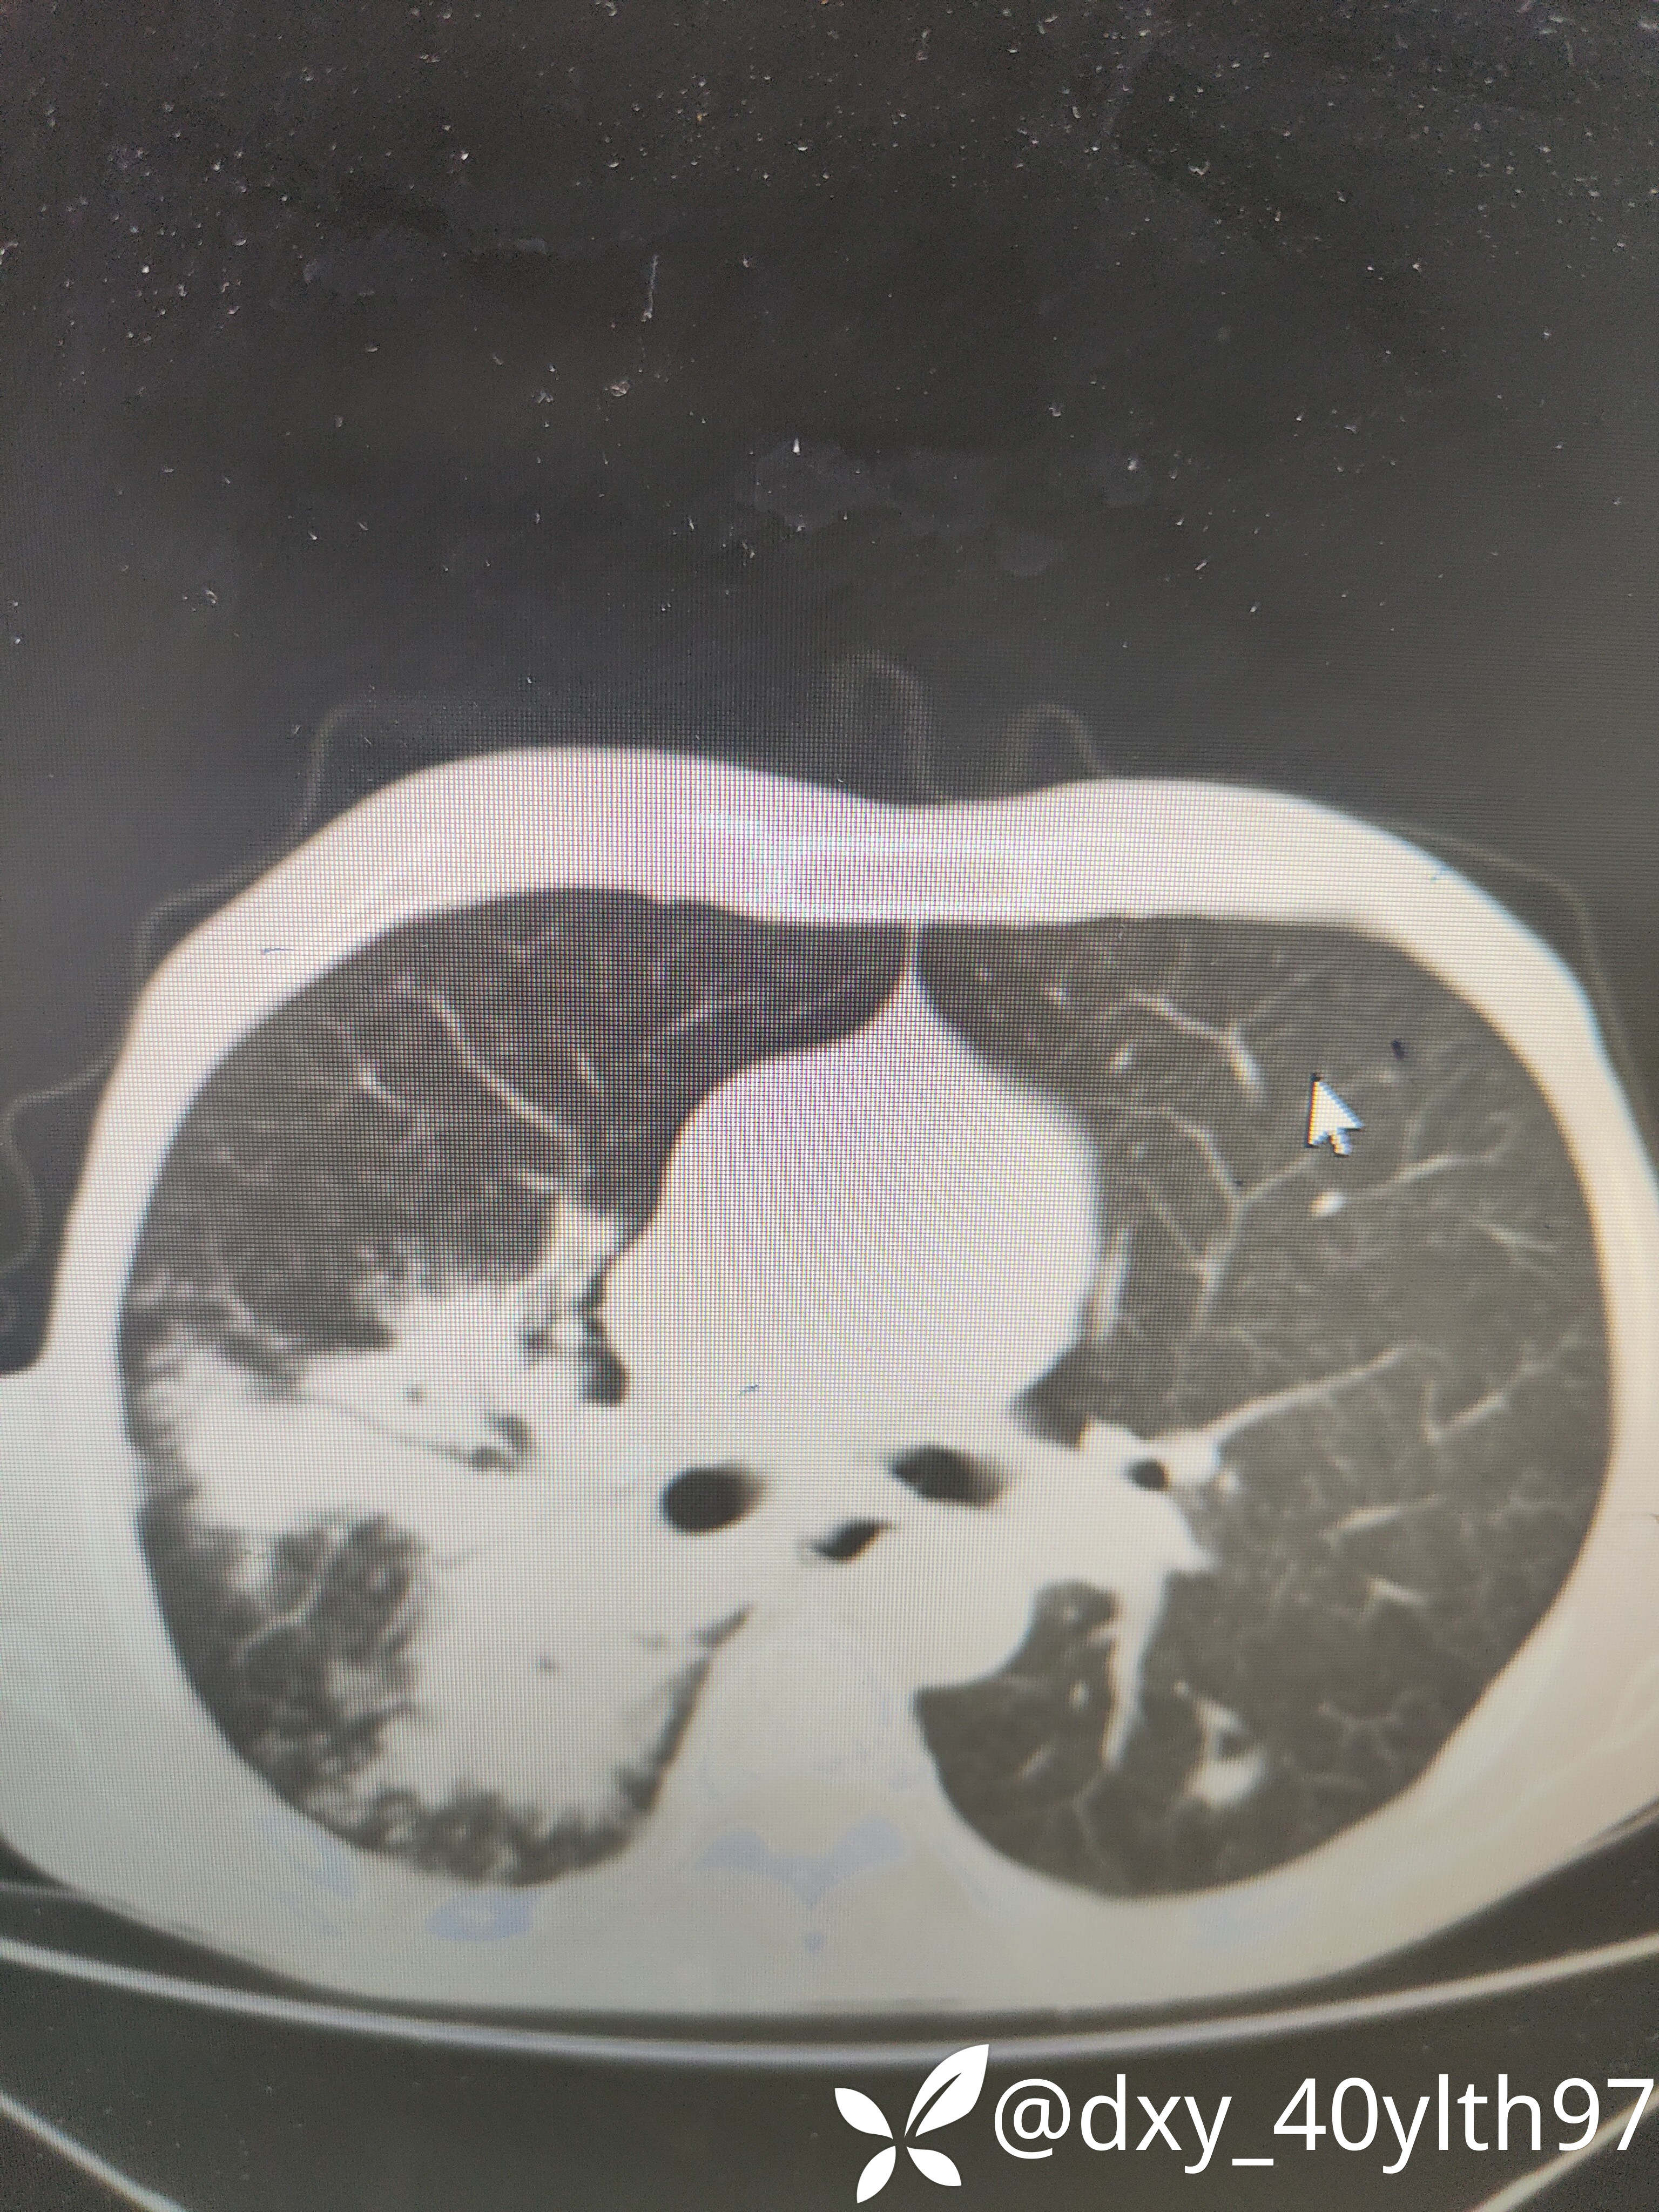

2021年5月首次肺部CT平扫,影像报告提示1.两肺慢性支气管炎、肺气肿、多发肺大疱;2.右肺中下叶多发感染性病变、结节、右肺门增大,建议治疗后复查或进一步检查排查右肺门区肿瘤性病变;3.左肺上段舌叶散在炎性病变

2021年8月因2型糖尿病入院复查肺部CT平扫,影像报告提示:胸部CT复查:1.右肺中下叶感染范围较前相仿、密度增高;2.右肺门区病变较前有所增大;3.右肺外基底段结节较前吸收。

2023年8月肺部CT平扫影像结果提示:1.右肺上叶密度增高影较前显著增大,建议进一步检查;2.两肺多发斑片结节灶较前增多,部分增大。

肺部增强CT影像学提示:右肺内大片不规则影轻度强化,肿瘤可能。